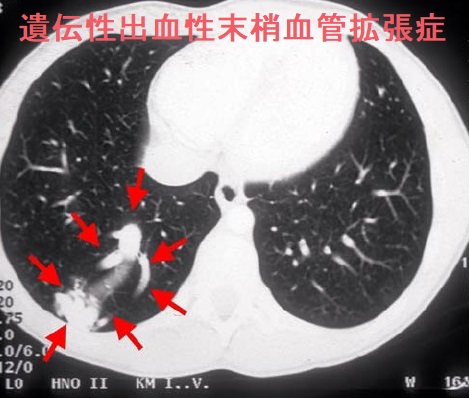

遺伝性出血性末梢血管拡張症(遺伝性出血性毛細血管拡張症、オスラー病、Osler-Weber-Rendu病)は、常染色体優性遺伝によって全身の血管奇形(異常な血管)が生じ、出血に至る病気です。出血が長く続くと、貧血になります。

- 鼻出血(80~90%)でほほ必須;耳鼻咽喉科で鼻腔粘膜の斑状発赤、びらんを確認してもらう

- じわじわ消化管出血、腹痛

- 口腔内出血

- 肺出血、血痰、肺動静脈奇形

- 頭痛やけいれん、脳動静脈奇形(AVM)

白斑、自己免疫性甲状腺炎(橋本病)、虹彩毛様体炎、骨髄異形成症候群(MDS)を合併した遺伝性出血性血管拡張症の報告があります。(Clin Exp Dermatol. 2005 Jul;30(4):448-50.)